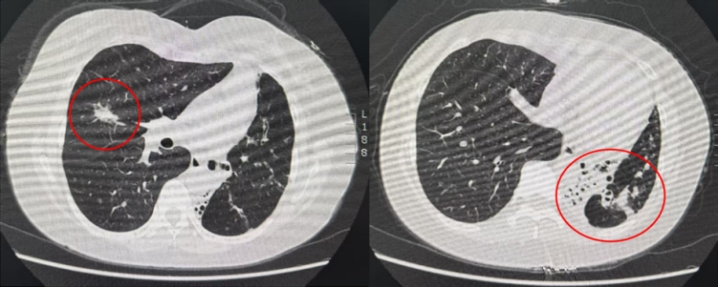

左图:右肺中叶结节(腺癌);右图:左肺下叶支扩病灶

张阿姨入院后,胸外科团队迅速展开病史询问并安排完善相关检查。胸部CT结果显示,患者双肺均存在支气管扩张,尤其是左肺呈现广泛的囊柱状扩张,左肺下叶损毁严重,纵隔明显向左侧偏移,左肺功能显著受限。肺功能检测显示FEV1(第一秒用力呼气量)仅占预计值的45%,而分侧肺功能检查进一步证实了患者及家属的担忧,右肺功能约占90%,左侧仅占10%左右——这意味着患侧(右肺)已经代偿了大部分肺功能,左肺的支气管扩张伴感染又需要术中进行隔离。